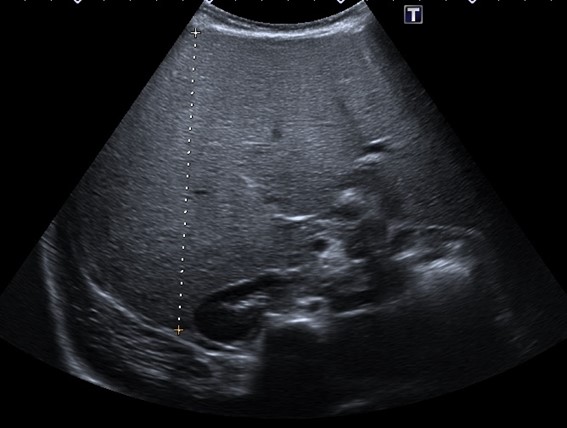

En la anamnesis, llama la atención la hiperfagia. Los padres refieren que come con mucho apetito y tiene hambre casi constantemente. También, la irritabilidad nocturna y la tendencia diaforética. En la exploración física, presenta aspecto macrosómico, con prominente panículo adiposo. Buena coloración de piel y mucosas, no ictericia. Abdomen distendido con hepatomegalia masiva de consistencia firme, hasta 12 cm bajo el reborde costal. No hay esplenomegalia. Exploración neurológica normal. En los análisis de sangre, presenta hipoglucemia (20 mg/dl) y elevación de transaminasas (GPT 289 U/l, GOT 550 U/l, GGT 125 U/l), hipertrigliceridemia (240 mg/dl) e hipercolesterolemia (280 mg/dl), creatin cinasa (CK) 89 U/l, lactato 1,3 mmol/l; con estudio de virus hepatotropos y autoinmunidad negativos. Estudio de coagulación normal. En la ecografía abdominal se visualiza una hepatomegalia masiva, con hiperecogenicidad difusa (Figs. 1 y 2). Ecocardiografía y exploración oftalmológica normales. Durante el ingreso, se llevan a cabo controles glucémicos, constatándose numerosas hipoglucemias de ayuno, todas ellas asintomáticas. Ante la sospecha de glucogenosis, se instaura tratamiento dietético con optimización de la ingesta de hidratos de carbono de absorción lenta, con lo que se consigue controles de glucemia normales previos al alta. Se realiza estudio metabólico sugerente de glucogenosis (oligosacáridos en orina: excreción elevada de hex4). En el estudio genético se objetiva variante patogénica c.556G>T(p.E186*) en el gen PHKG2 en aparente homocigosis, compatible con el diagnóstico de enfermedad de almacenamiento de glucógeno tipo 9C.

Figura 1. Gran hepatomegalia con hiperecogenicidad difusa. Se muestra el eje longitudinal del hígado (14,3 cm), muy aumentado de tamaño para la edad de la menor